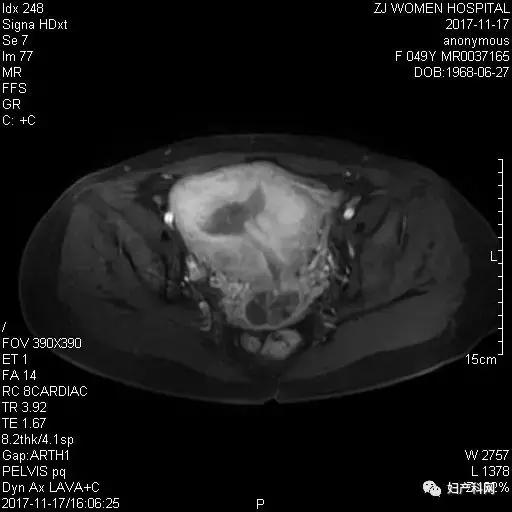

术后行盆腔MRI增强扫描,了解肌瘤大小及周围组织情况:子宫显示,明显增大,形态失常,宫区见7-8个大小不等占位灶,部分向外凸起,表面凹凸不平,最大位于子宫后壁约8.9x7.5x8.5cm,边界尚清楚,内膜信号欠均匀,内见絮片状强化影,宫颈内见2.6x3.4x3.8cm长T1长T2为主囊泡样信号影,增强后轻度强化。左侧卵巢见长径约4.5cm囊性灶,边界清楚,未见明显强化,右侧卵巢显示,大小形态及信号未见明显异常。盆底未见积液。诊断结果:子宫多发肌瘤;宫腔及颈管多发息肉;左侧卵巢囊肿。